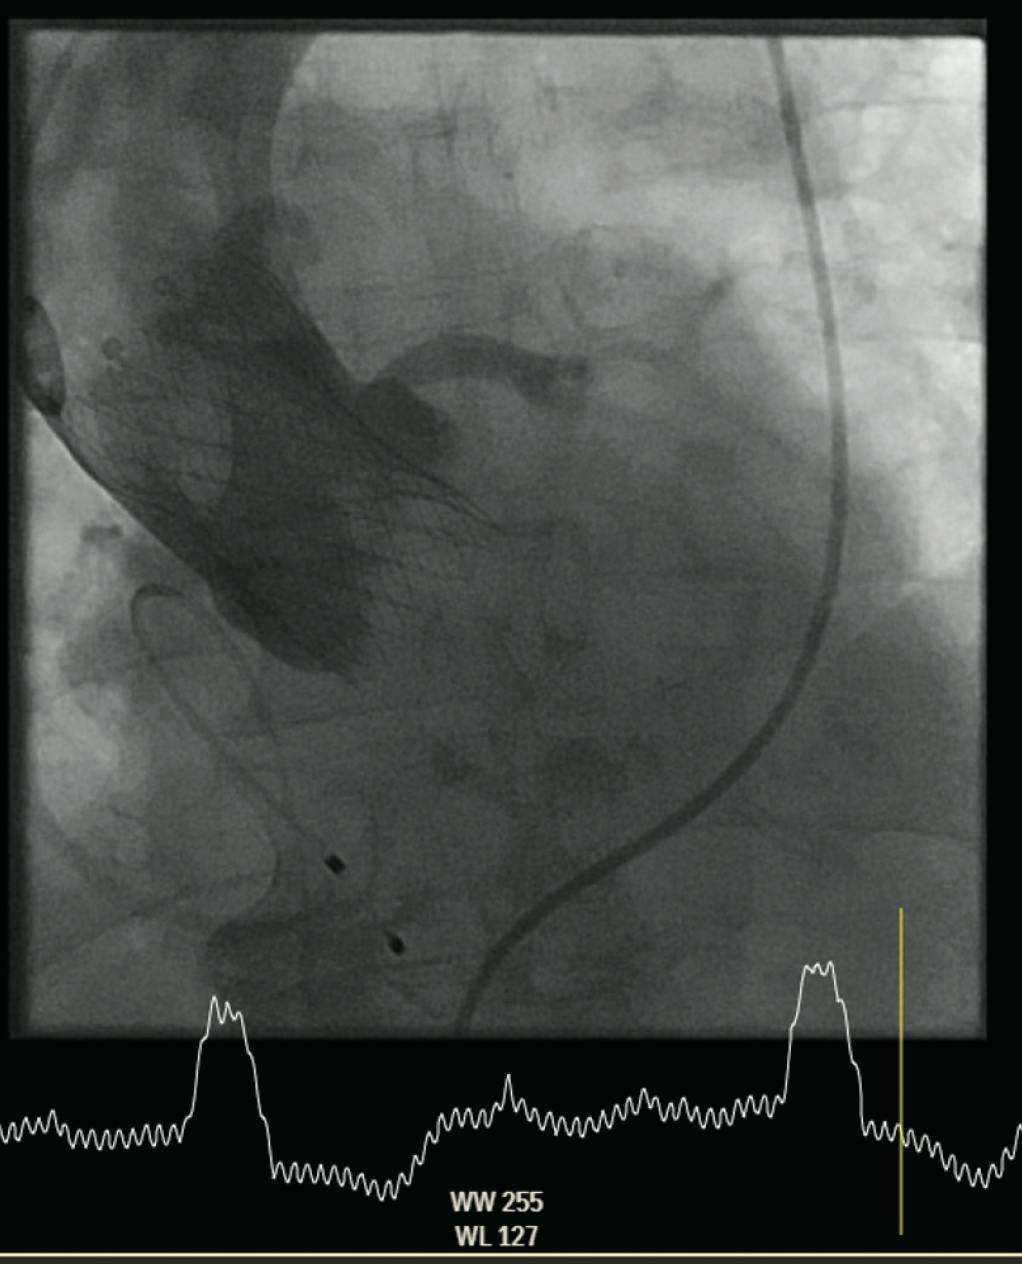

If the targeted implantation depth has been achieved and there is no relevant paravalvular leakage, the Evolut Pro THV can be completely released in a slow manner as described previously to minimize any potential movement (Figure 5).

Figure 5. Final aortography after deployment showing optimal implantation depth and no paravalvular leak.